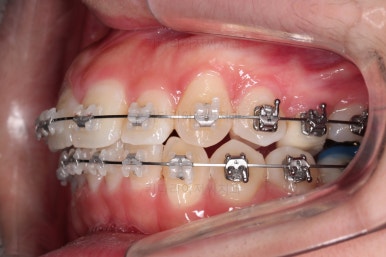

앞에서 봤을 때 치열은 가지런해졌지만 기울어진 느낌을 조금이라도 잡아보고자 미니스크류를 이용해서 입매 개선 및 기울기 개선을 시도했습니다.

미니스크류가 구성되었고요.

기울기와 돌출입을 개선하고자 이러저리 밀고당고 하는 모습입니다.

오히려 이전 사진보다 치열이 더 틀어지고 잘 안맞는 모습이죠?